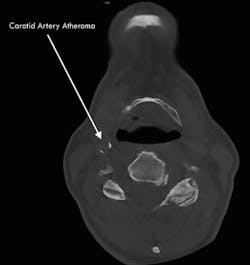

Uncovering incidental findings has had a large impact on our bottom line. Without the right equipment and training, we would not be able to detect or diagnose any of the dental mysteries that are causing patients discomfort. 3-D imaging helps us identify pathology that is unable to be seen on traditional x-rays. And, to some degree, it has made an impact on patients’ lives. We have had three patients in the last couple of years who have had arterial blockages, putting them at a significantly higher risk for stroke. CBCT diagnostics with a large field of view completely turned around the life of one of these patients. We discovered risks for sleep apnea and addressed those; we also uncovered a blockage that, if not addressed, could have dramatically altered the patient’s life.